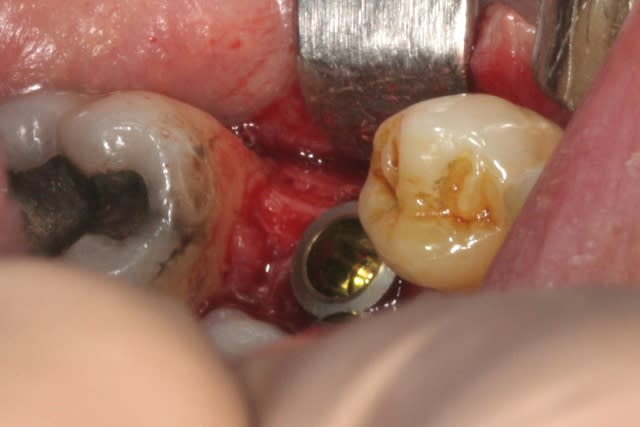

place aux photos!!!

forage, tout ce qu'il y a de plus classique pour ceux qui connaissent ID ou zimmer

pour un implant de 5mm de diamètre on s'arrête au foret de 4.4, passé ici sur 8mm au lieu des 11.5mm car j'étais dans du D3

l'interactive, (t'ain qu'il est beau!!!)

mise en place au CA qui bloque à 45Ncm...on est à 1 ou 2 mm de la crête....pas de problème, on retire le Fm (sympa, la vis, car il y a un filetage dans le Fm, ne risque plus de tomber!!!) et on se reprend direct dans le col de l'implant à la clef à cliquet...comme d'hab quoi...;-)